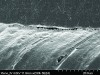

Figure 1. This canning electron microscope (SEM) image reveals a restorative material properly bonded to enamel and dentin that provides the potential for long-term functional success. (Courtesy of Jorge Perdigão, DMD, MS, PhD.)

Figure 1

Figure 2. This SEM view illustrates a restorative material improperly bonded to enamel and dentin that can result in clinical failure. (Courtesy of Jorge Perdigão, DMD, MS, PhD.)

Figure 2